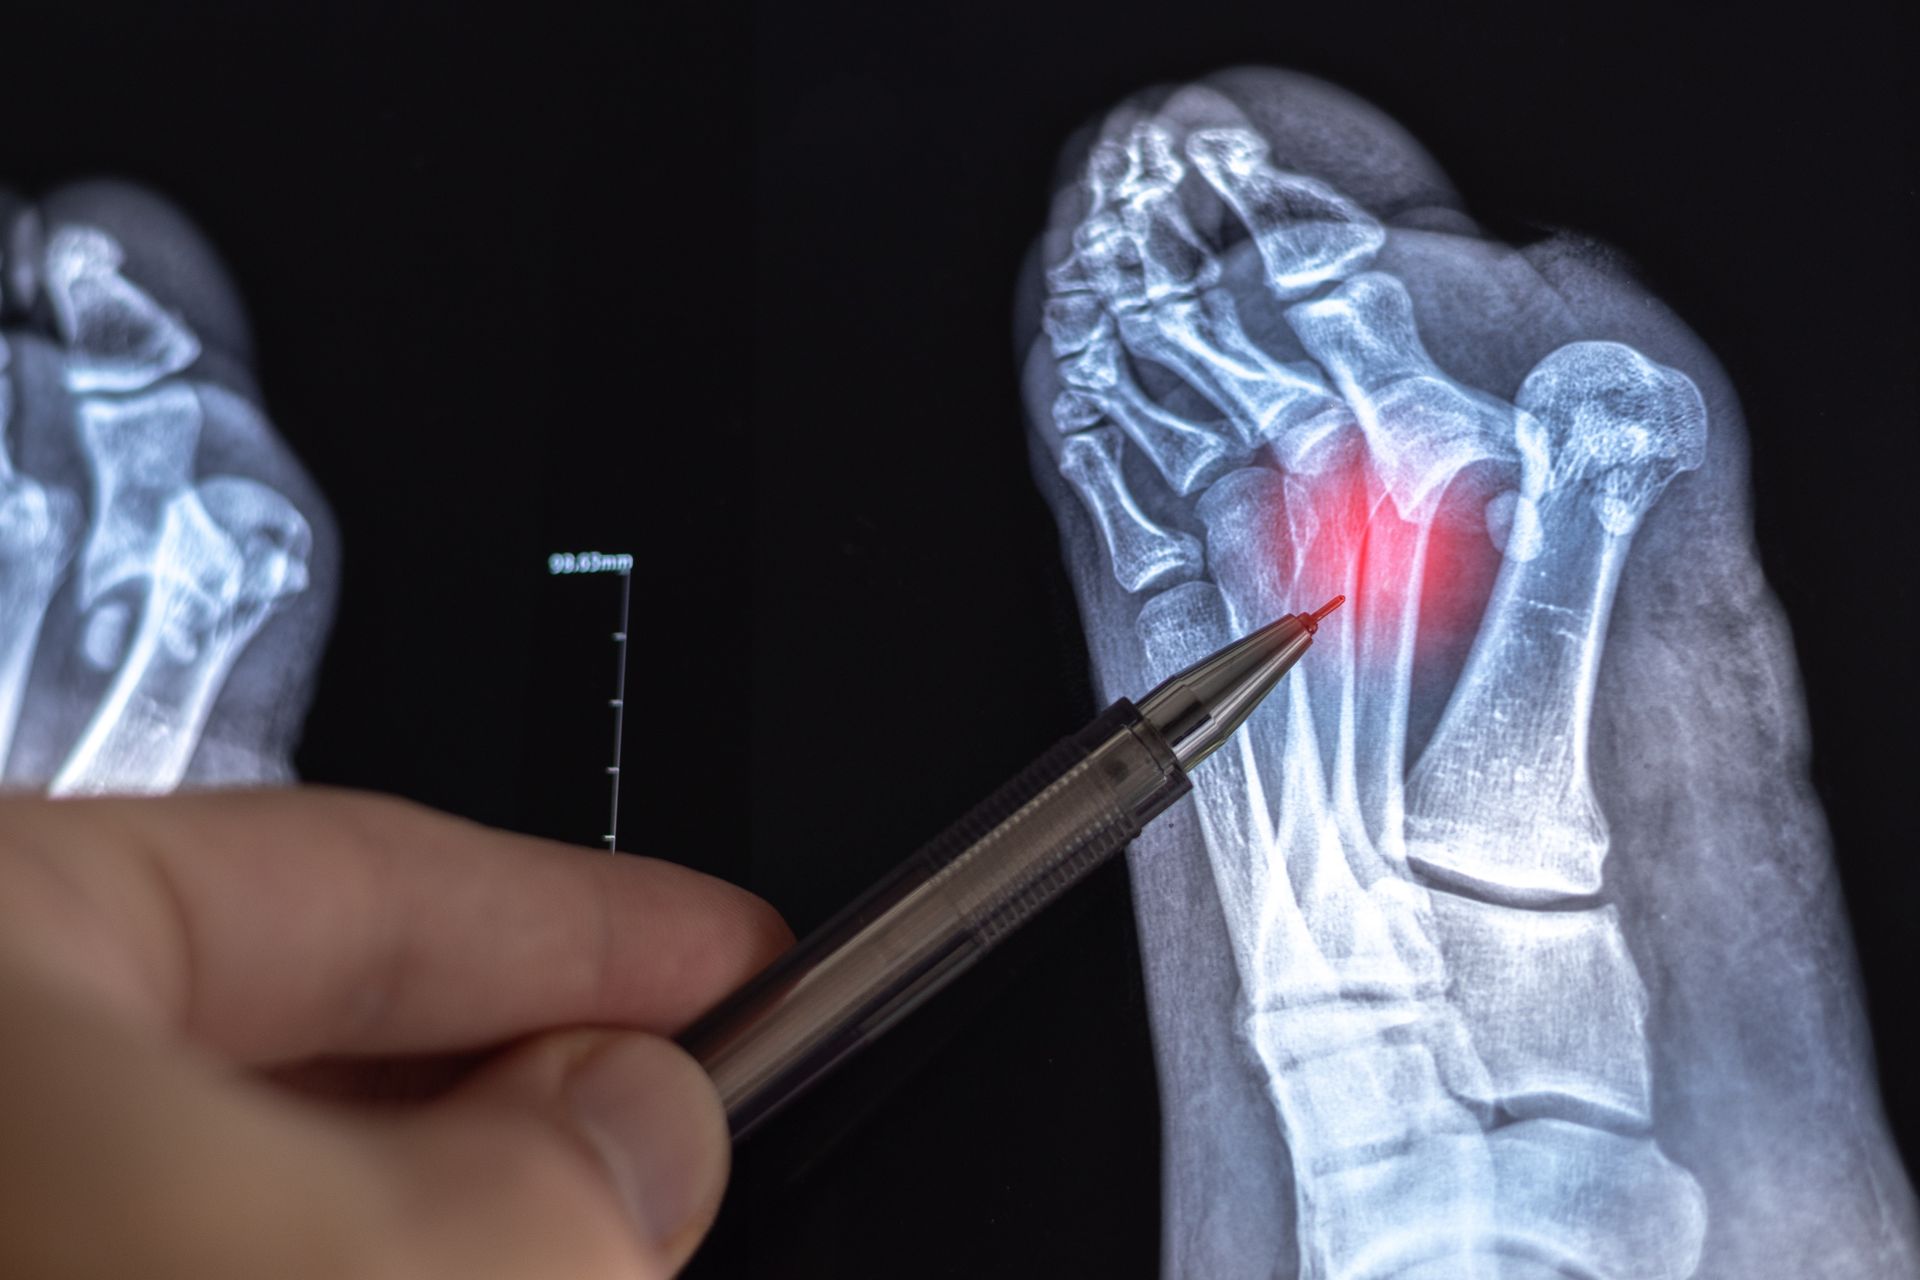

Foot and ankle fractures occur when one or more of the bones in the foot or ankle break due to trauma, overuse, or repetitive stress. These injuries can range from minor hairline cracks to complex breaks that affect joint stability and mobility. Common causes include falls, sports injuries, car accidents, or even twisting the ankle during daily activities. Prompt diagnosis and proper treatment are essential to ensure optimal healing and prevent long-term complications.

We provide comprehensive evaluations using advanced imaging to determine the type, location, and severity of your fracture. Based on these findings, we develop individualized treatment plans that may include immobilization with a cast or walking boot, protective bracing, rest and elevation, or physical therapy to restore strength and flexibility. In cases of severe or displaced fractures, surgical intervention may be necessary to realign and stabilize the bones for proper healing.